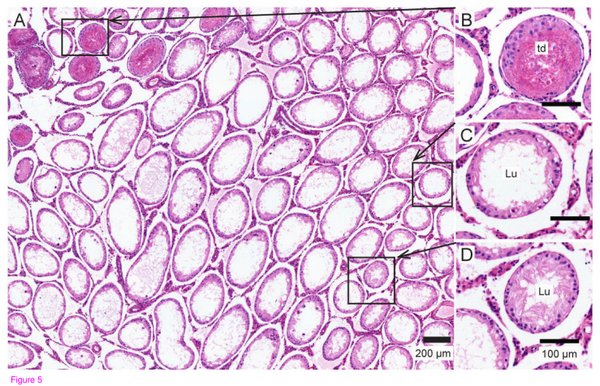

经过频率为3兆赫超声波处理过后的睾丸组织,可以看到部分生精小管(睾丸中进行减数分裂产生精子的场所)由于受热收到了伤害(td),而更多的生精小管内则产生了空腔(lu)。

未经处理和只经过热处理的睾丸组织。在A-D中,未经处理的生精小管内可以看到精母细胞(sp),浓缩的精子细胞(cs)和圆形的精子细胞(rs)。在经过热处理之后(E-H)可以看到生精小管内精子变少,表皮变薄(e),并且内部有空腔产生(lu)。